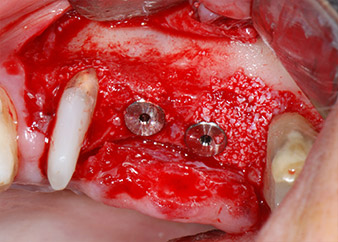

Имплантите (Restore, Keystone Dental, диаметър 3,75 mm, дължина 8.0 mm) са поставени с имплантологичен мотор

(Фиг. 11 и 12).

Поставяне на имплант 26 на ниски обороти

Фиг. 11: Поставяне на имплант 26 на ниски обороти с ограничение на въртящия момент 35 Ncm.

готовност за покривни винтове

Фиг. 12: Двата импланта са на място и са готови за поставяне на покривни винтове.